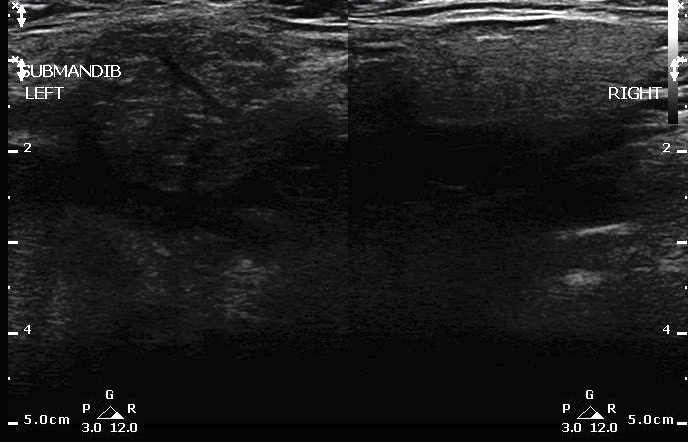

- Comparison of Sialadenitis on the left and normal submandibular gland on right:

- Figure 21. Sialadenitis (left) vs normal (right)

- Submandibular gland sialoadenitis/sialolithiasis:

- Appears heterogeneous with dilatation of the salivary ducts.

- Increased vascularity can be seen on Doppler.